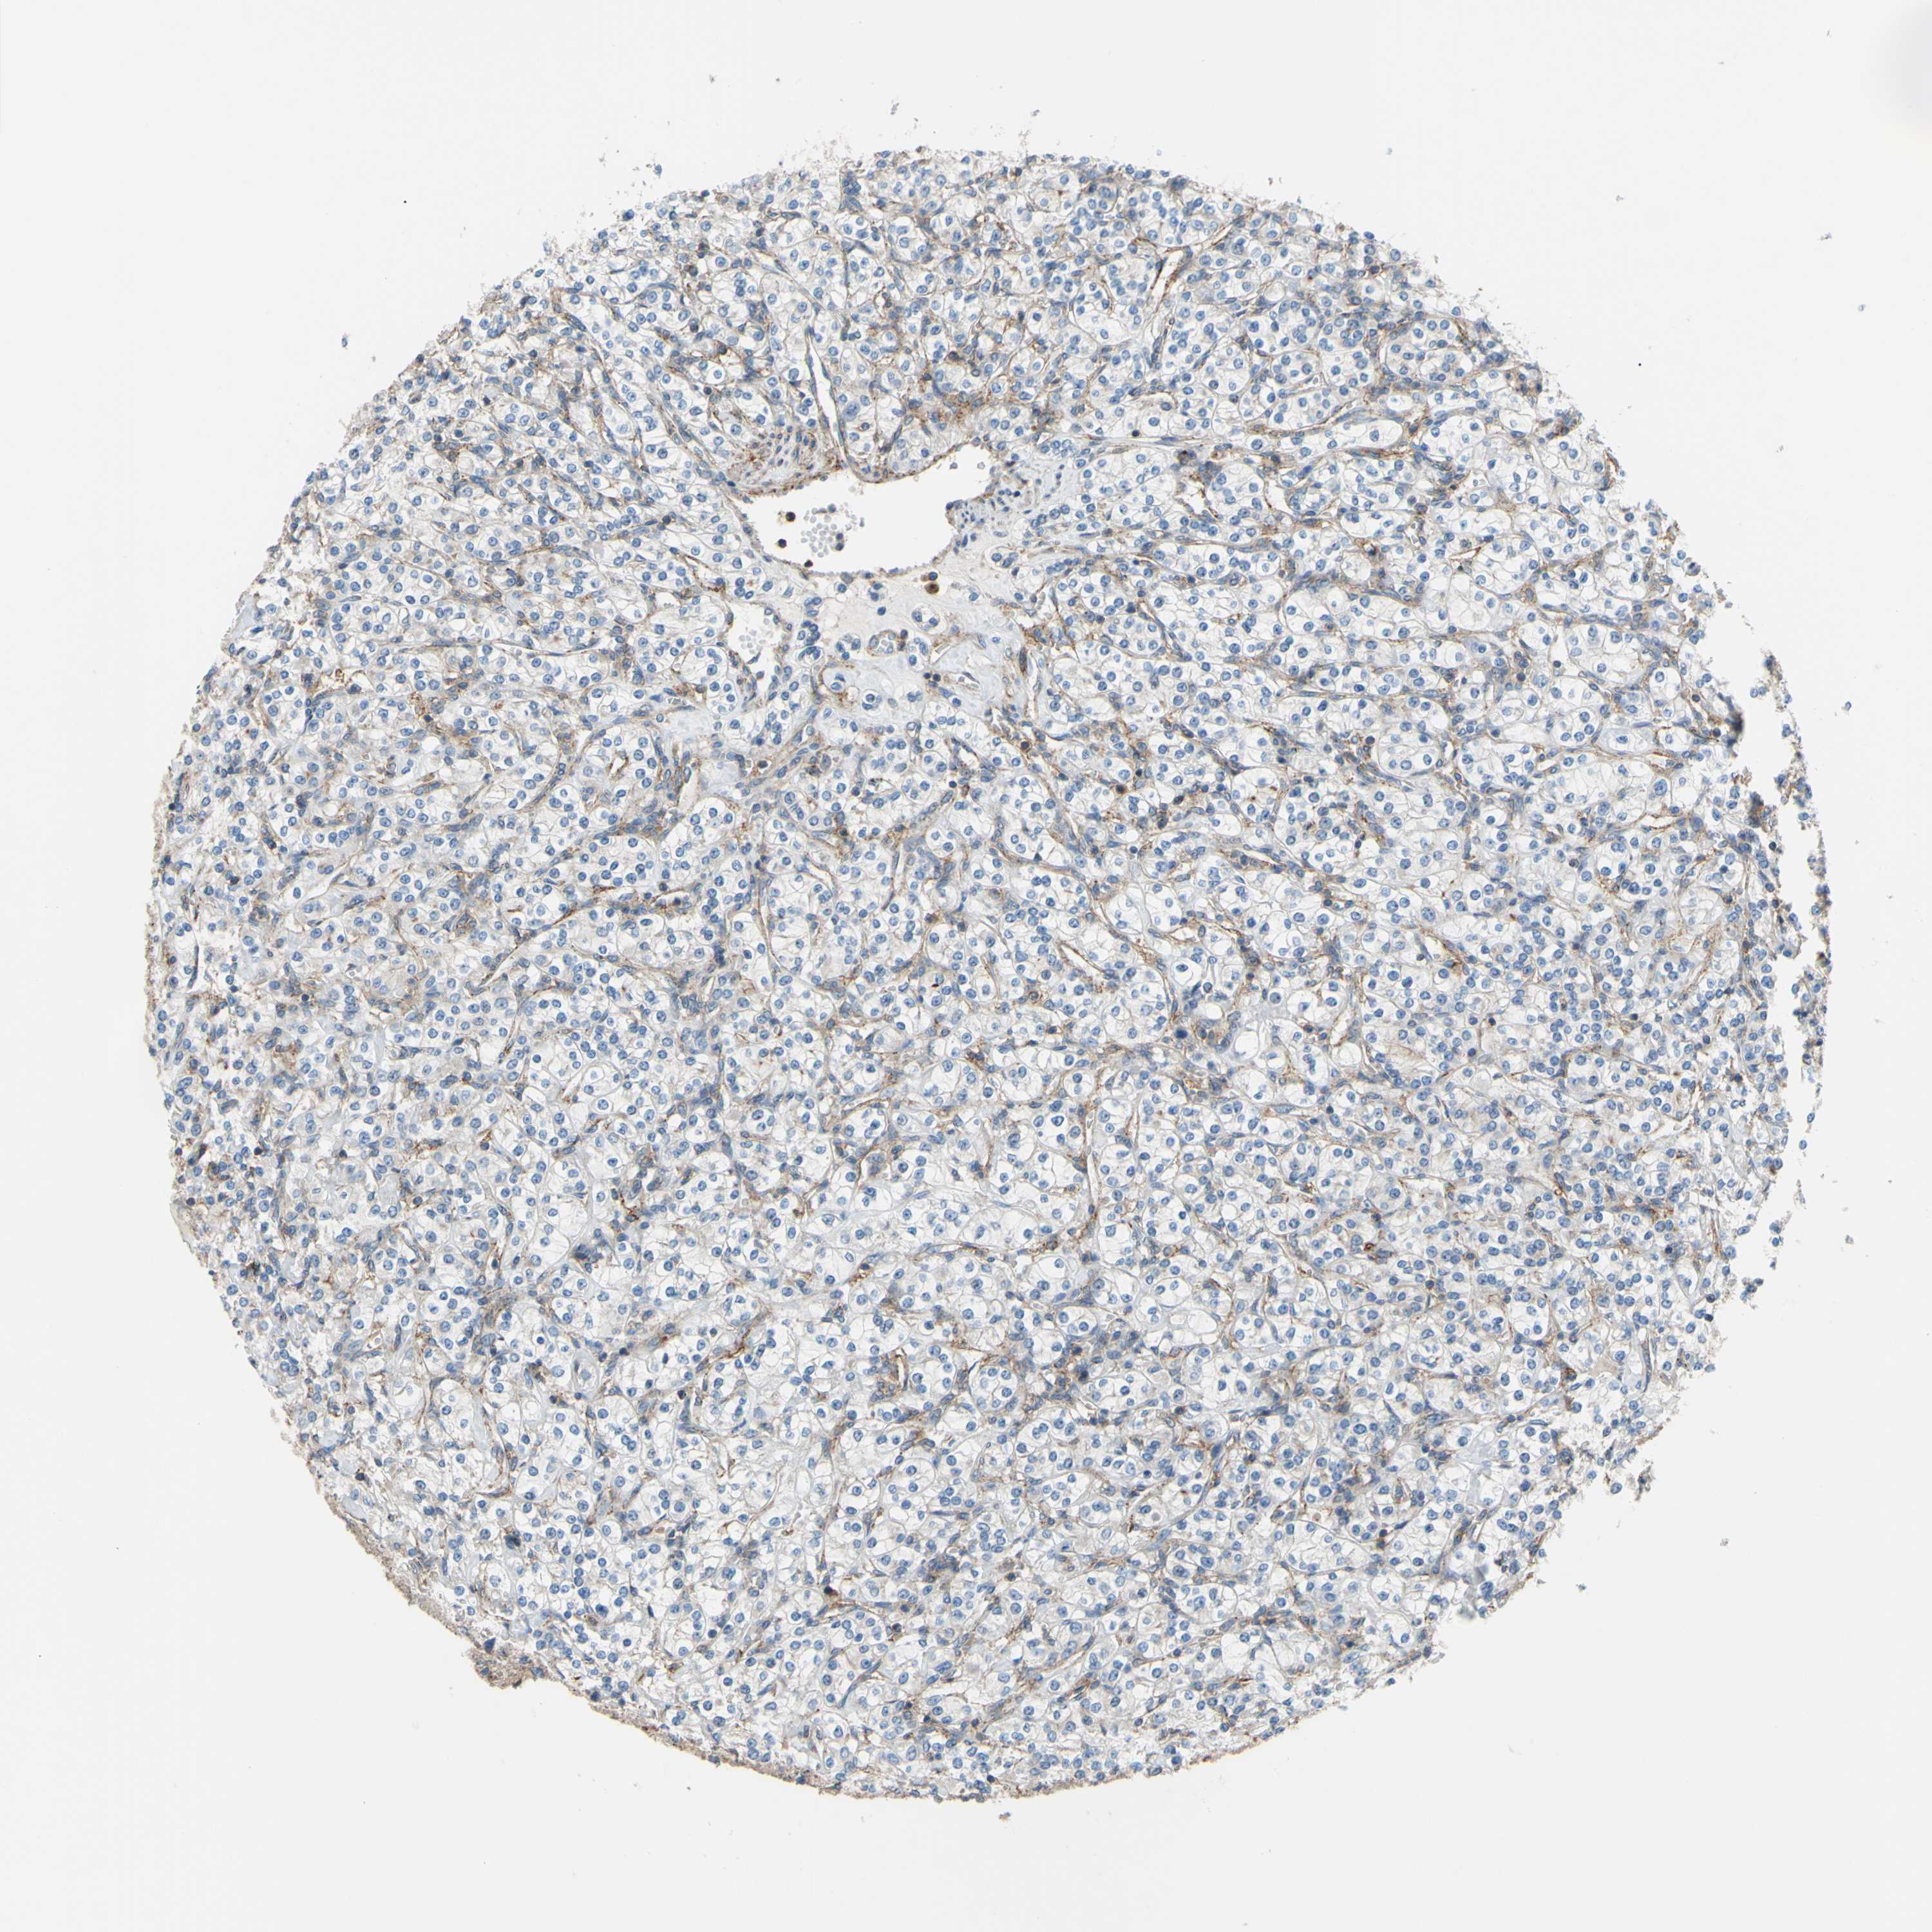

KIDNEY RENAL CLEAR CELL CARCINOMA (TCGA) - Interactive survival scatter ploti

The Survival Scatter plot shows the clinical status (i.e. dead or alive) for all individuals in the patient cohort, based on the same data that underlies the corresponding Kaplan-Meier plots. Patients that are alive at last time for follow-up are shown in blue and patients who have died during the study are shown in red.

The x-axis shows the expression levels (FPKM) of the investigated gene in the tumor tissue at the time of diagnosis. The y-axis shows the follow-up time after diagnosis (years). Both axes are complimented with kernel density curves demonstrating the data density over the axes. The top density plot shows the expression levels (FPKM) distribution among dead (red) and alive patients (blue). The right density plot shows the data density of the survived years of dead patients with high and low expression levels respectively, stratified using the cutoff indicated by the vertical dashed line through the Survival Scatter plot. This cutoff is automatically defined based on the FPKM cutoff that minimizes the p-score. The cutoff can be changed by dragging the vertical line or by entering a cutoff value in the square labeled "Current cut-off".

Under the Survival Scatter plot the p-score landscape (black curve; left axis) is shown together with dead median separation (red curve; right axis). Dead median separation is the difference in median mRNA expression between patients who have died with high and low expression, respectively. It is calculated as follows: median FPKM expression of dead patients with high expression - median FPKM expression of dead patients with low expression. This is intended to aid the user in visually exploring custom cutoffs and the associated p-scores and dead median separation.

Individual patient data is displayed and can be filtered by clicking on one or more of the category buttons on the top of the page. Categories describing expression level and patient information include: high, low, alive, dead, female, male and tumor stages. The scale of the x-axis can be toggled between linear and log-scale by clicking on the "x log" button. Mouse-over function shows TCGA ID, patient information and mRNA expression (FPKM) for each patient.

& Survival analysisi

Kaplan-Meier plots summarize results from analysis of correlation between mRNA expression level and patient survival. Patients were divided based on level of expression into one of the two groups "low" (under cut off) or "high" (over cut off). X-axis shows time for survival (years) and y-axis shows the probability of survival, where 1.0 corresponds to 100 percent.

POR is potential prognostic, high expression is favorable in Kidney Renal Clear Cell Carcinoma (TCGA)

Best expression cut offi

Based on the FPKM value of each gene, patients were classified into two groups and association between prognosis (survival) and gene expression (FPKM) was examined. The best expression cut-off refers the FPKM value that yields maximal difference with regard to survival between the two groups at the lowest log-rank P-value. Best expression cut-off was selected based on survival analysis .

When clicking on this number, the vertical dashed line indicating cut-off, the interactive survival plot, and the Kaplan-Meier curve will be adjusted to show results based on the best expression cut-off.

: 32.71

TCGA RNA samplesi

RNA-seq data is reported as average FPKM (number Fragments Per Kilobase of exon per Million reads), generated by the The Cancer Genome Atlas (TCGA) .

Normal distribution across the dataset is visualized with box plots, shown as median and 25th and 75th percentiles. Points are displayed as outliers if they are above or below 1.5 times the interquartile range. FPKM values of the individual samples are presented next to the box plot.

Average pTPM 42.9

Number of samples 521